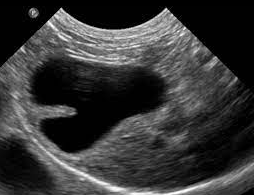

고양이 2중 담낭에 대한 분류

보통 고양이 복부 초음파를 볼때 담낭이 2개인 친구들이 종종 관찰된다.

그 자체로는 아무런 임상적 의미가 없기 때문에 크게 고려 대상이 되지는 않지만